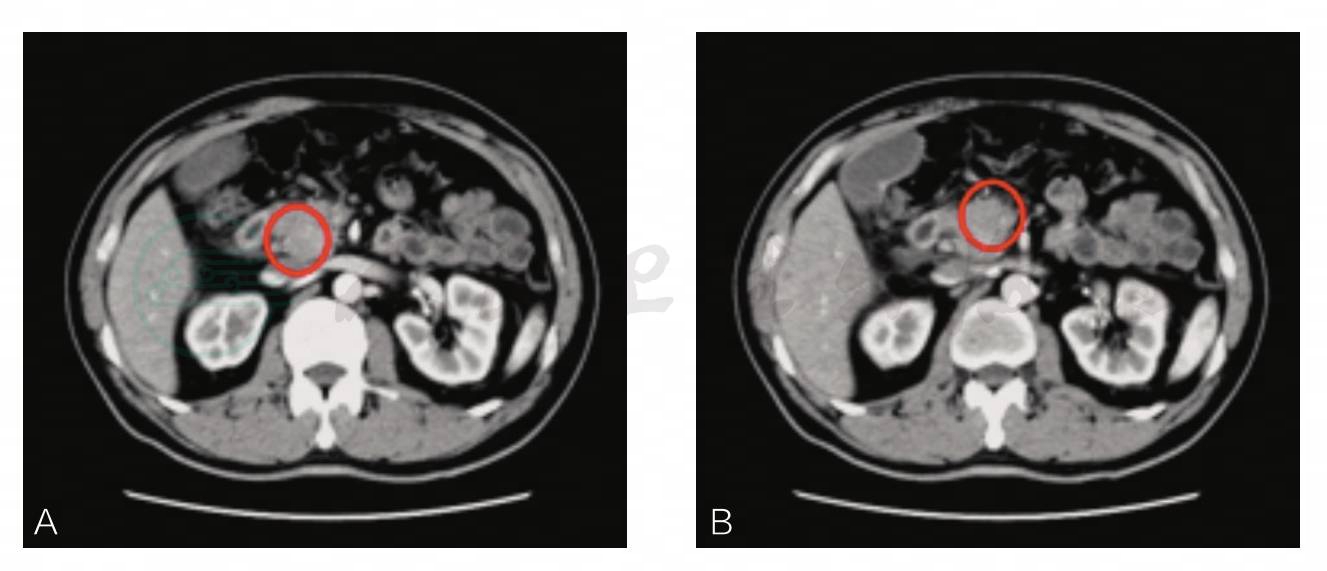

图2 术后第6周CT影像

胰十二指肠切除术后改变,胰腺肿胀(圆圈所指),肝内胆管扩张明显(箭头所指),肝门区胆管壁增厚

激素治疗8周后:TB 18.9μmol/L,DB 1.3μmol/L,恢复正常水平;类风湿因子21U/ml;IgG 1170mg/dl;IgA 200mg/dl(正常值:82~453mg/dl);IgM 154mg/dl(正常值:46~304mg/dl)。CT提示:胰十二指肠切除术后改变,胰腺形态基本恢复正常(箭头所指),胆道扩张积气较前改善(图3)。

图3 激素治疗后第8周CT影像

胰十二指肠切除术后改变,胰腺形态基本恢复正常(箭头所指),胆道扩张积气较前改善